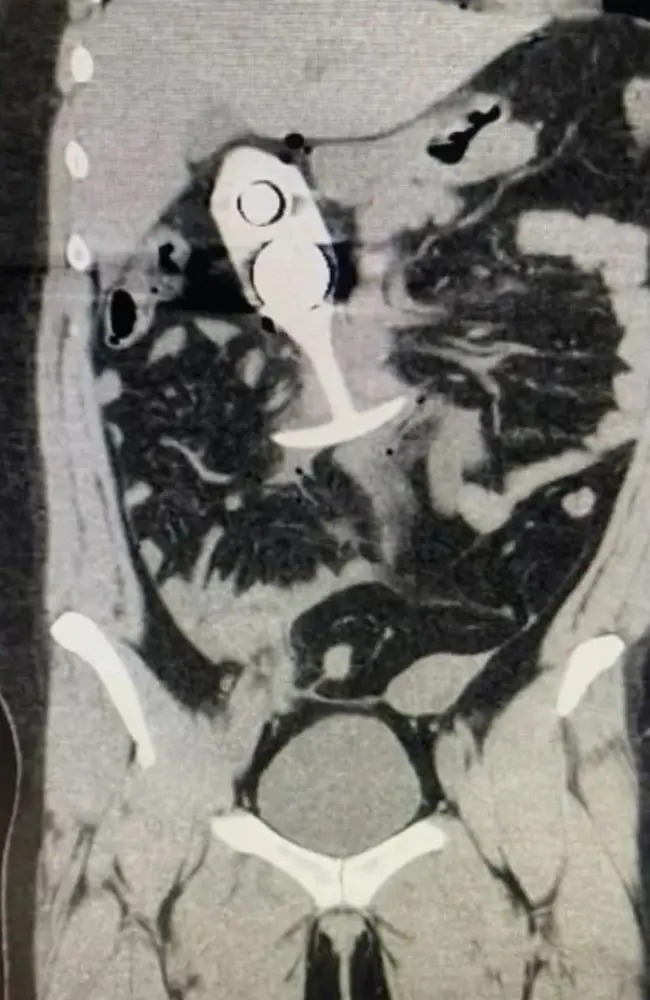

雖然這宗事件發(fā)生在2023年4月,但據(jù)稱顯示患者事發(fā)后掃描的圖像,最近開始在網(wǎng)上流傳,提示人們不要在掃描期間佩戴任何金屬物品。

肛塞穿過女子身體,致她身受重傷。 路透社

▲肛塞穿過女子身體,致她身受重傷。 路透社